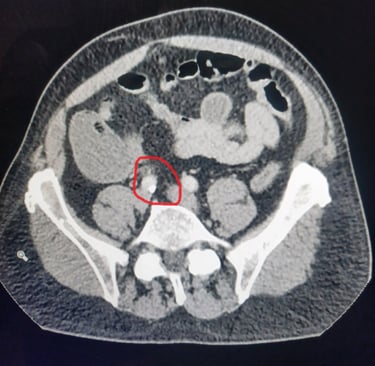

I woke in the morning and decided if I was going to get back on the road I should start eating, so I ate as much breakfast as I could. After an hour I felt worse than ever. So I decided it was time to go to the ER. By the time I got there I was actually crying. I’m not sure if it was from the pain or just relief. The doctor decided to take a CT Scan to see what was going on and offered me a some pain relief. I told him I was alone and needed to drive so he offered a non-narcotic option. I decided to hold off until we knew more. The CT Scan revealed that I had a 5mm kidney stone. At this point I asked if the pain killer worked and he said it usually did, so they injected me with something and it worked. I walked out feeling better and filled some prescriptions, one for Meloxicam, my favorite magic pill. I returned to the Hampton Inn and all that laxative started doing its job, in spades. I decided I would stay another day as my flight out Phoenix had already taken off.